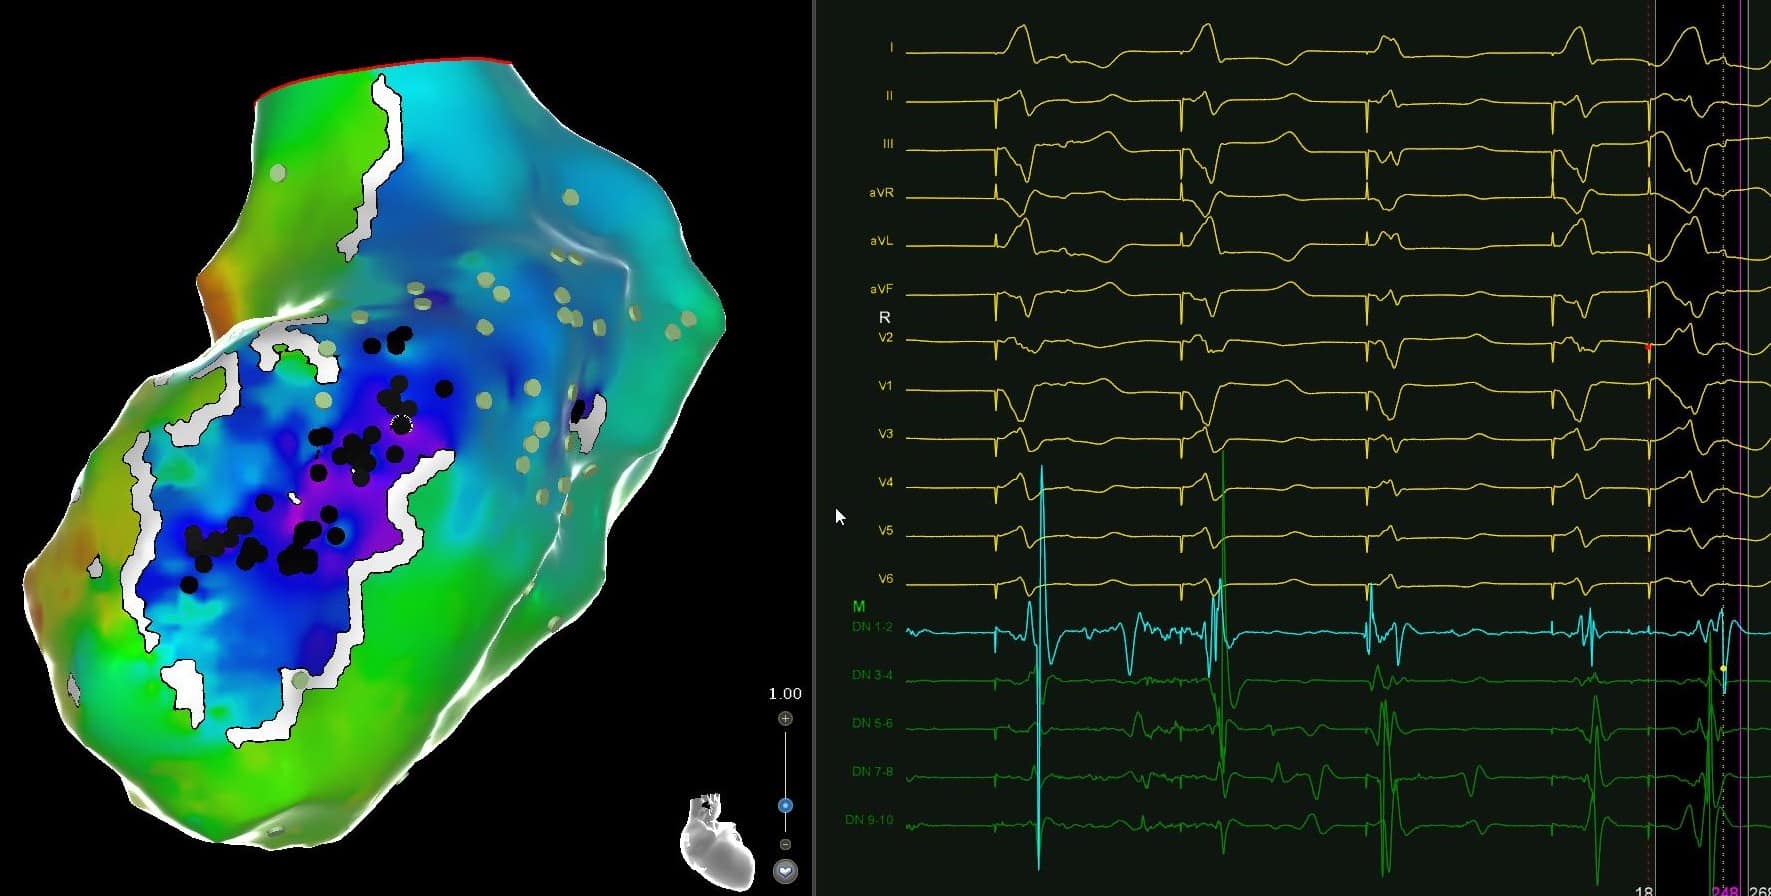

3D Mapping in Action

Created by an EP fellow enrolled in EP in Practice. Real‑world impact, in real-world labs.